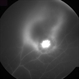

- Toxoplasmosis Chorioretinitis Case 2

- Above the optic nerve there was evidence of a Weiss ring. Not unusual since Toxoplasmosis chorioretinitis is a cause of a premature posterior vitreous detachment.